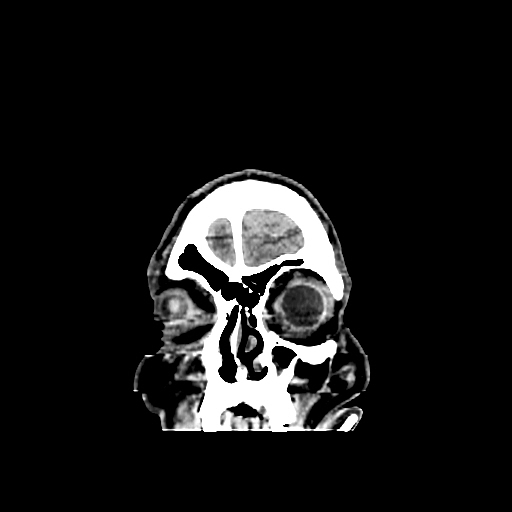

A 60 years old man with seizure since 12 years

Plan CT scan was done on 22 march 2016